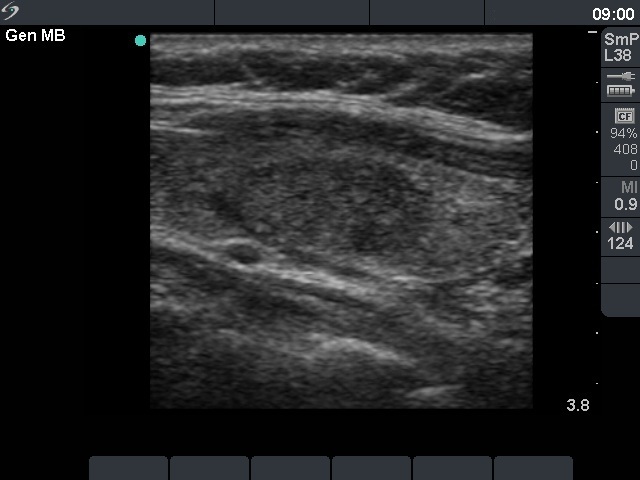

First examination (1st and 2nd rows of images)

Clinical presentation: a 45-year-old woman was referred for evaluation of a nodule discovered by carotid Doppler examination.

Palpation: a not firm nodule in the left lobe.

Functional state: euthyroidism with TSH-level 1.33 mIU/L.

Ultrasonography. The thyroid was echonormal. There was a moderately hypoechogenic, inhomogeneous nodule in the part of the left lobe. The nodule presented a type 3 vascular pattern.

Cytological pattern corresponded to a follicular tumor without significant atypia.

A combined clinical-ultrasound-cytological diagnosis was benign follicular proliferation with less than 1% risk of carcinoma.

We advised regular follow-up instead of immediate surgery.